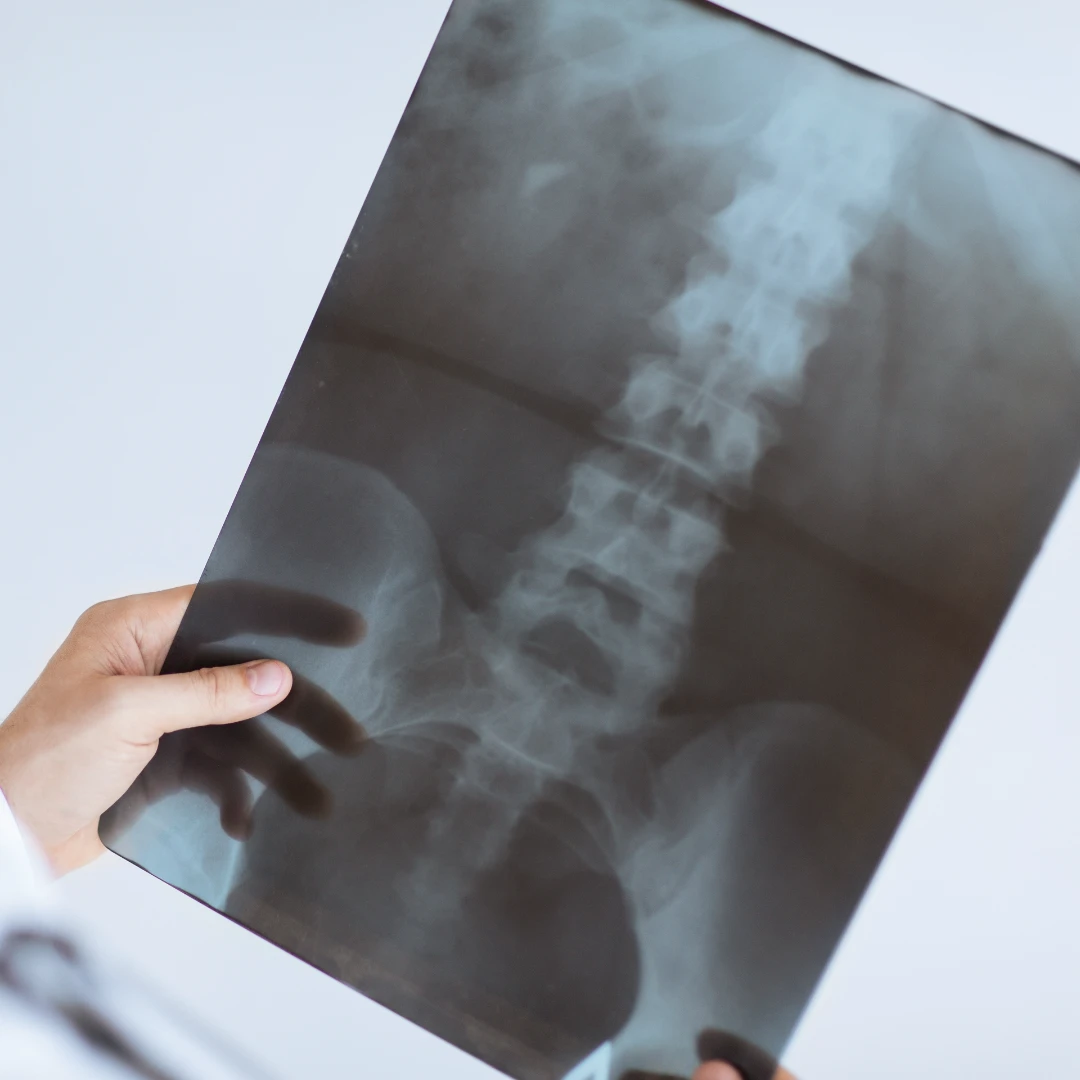

X-rays are a common medical imaging tool used to visualise the body's anatomy beneath the skin – this includes visualising the bones, internal soft tissues, and organs. X-rays are immensely useful in diagnosing and ruling out bone fractures, joint dislocations, and soft tissue injuries and are safe, cost-effective, and clinically effective in evaluating a person’s health.

X-rays can be performed on various parts of the body. This makes X-rays unique, versatile, quick, and effective in assisting the physician to reach the correct diagnosis.

Spine X-ray: allows scanning of the bony and soft tissue structure and overall spine alignment.